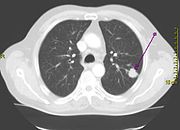

![]() Cross section of a human lung. The white area in the upper lobe is cancer; the black areas indicate that the patient was a smoker. |

Lung cancer may be seen on chest x-ray and computed tomography (CT scan). The diagnosis is confirmed with a biopsy. This is usually performed via bronchoscopy or CT-guided biopsy. Treatment and prognosis depend upon the histological type of cancer, the stage (degree of spread), and the patient's performance status. Possible treatments include surgery, chemotherapy, and radiotherapy. With treatment, the five-year survival rate is 14%.

Performing a chest x-ray is the first step if a patient reports symptoms that may be suggestive of lung cancer. This may reveal an obvious mass, widening of the mediastinum (suggestive of spread to lymph nodes there), atelectasis (collapse), consolidation (pneumonia), or pleural effusion. If there are no x-ray findings but the suspicion is high (such as a heavy smoker with blood-stained sputum), bronchoscopy and/or a CT scan may provide the necessary information. Bronchoscopy or CT-guided biopsy is often used to identify the tumor type.

If investigations confirm lung cancer, CT scan and often positron emission tomography (PET) are used to determine whether the disease is localised and amenable to surgery or whether it has spread to the point where it cannot be cured surgically.